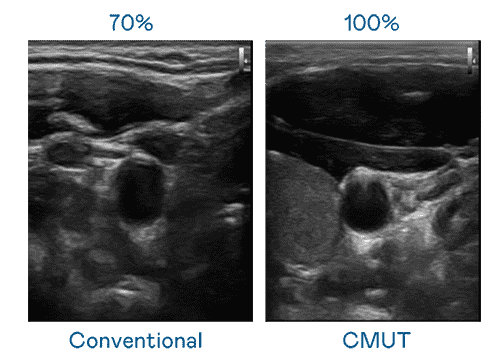

CMUT 技术是一种用电容式微机电元件来产生超音波讯号的技术。。。与传统 PZT 压电式技术相比,,CMUT 频宽增加 30%,,,,更宽频的超音波讯号让影像解析度大幅提升,,,,是实现高影像品质医疗超音波扫描、、促进精准医疗发展的关键技术。。

大频宽带来超清晰影像

超音波影像的解析度高低,,,首先取决于探头能发出的讯号频宽。。尊龙集团 CMUT 可提供高清晰的超音波讯号,,提供高频宽、、、高灵敏度、、、、影像纹理细节更高的超音波影像,,,协助医护人员缩短影像判读时间及利用精准的医疗影像进行诊断。。。。